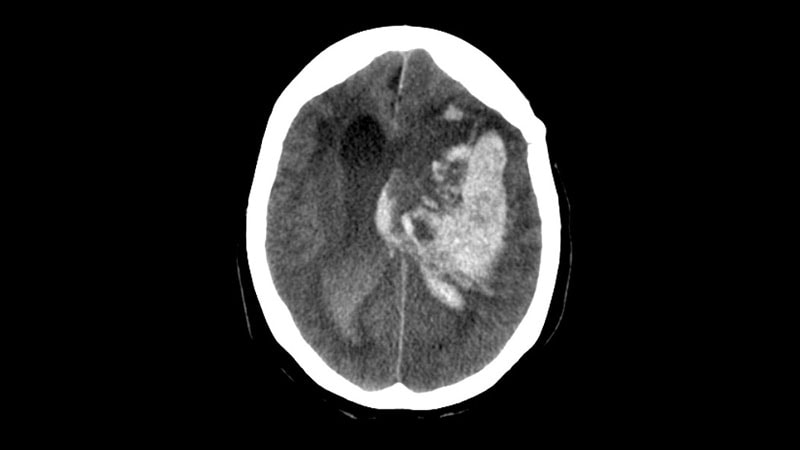

INTERACT3 looked at the rapid blood preasure reduction, anti-pyrexia treatment and reversal of anticoagulation in 7036 patients with acute ICH ➡️ and showed strong effects on 90-Day outcome (0.8, 0.7-0.9). NNT = 35. Congratulations to all the investigators! #ESOC2023

The INTERACT3 cluster randomized trial: Implementation of a care bundle improved functional outcome, reduced mortality, and had fewer serious adverse events in patients with intracerebral hemorrhage. #ESOC2023 #ESOC @ESOstroke

INTERACT3 shows that care bundle addressing BP, glucose, temp leads to improved outcomes among patients with ICH with NNT of 35. #ESOC2023

#INTERACT3 implemented an intensive care bundle with BP reduction & management of hyperglycaemia, pyrexia & abnormal anticoagulation for #ICH patients in a stepped-wedge cluster #RCT Compared to standard care, the bundle improved functional outcome in #ICH patients #ESOC2023 👇